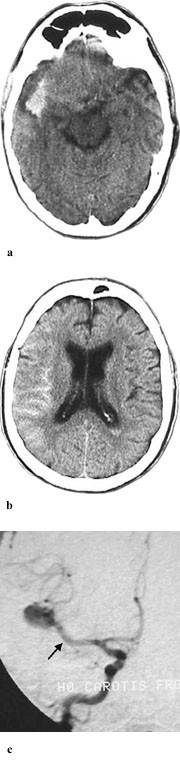

Spinalpunksjon var positiv for blod hos alle pasienter med negativ CT-funn (n = 6). Av disse var tre undersøkt på Advantage-maskinen og tre på Philips-maskinen. Hos en pasient var det angitt xantokromi (gul spinalvæske). CT-undersøkelse viste tegn på økt intrakranialt trykk hos en av disse pasientene. Cerebral angiografi viste intrakranialt aneurisme hos fire, men var normal hos to av disse pasientene. Det gikk lengre tid fra symptomdebut til CT-undersøkelse hos pasienter med negative CT-funn i forhold til dem med positive CT-funn (median 87 timer mot 3 timer og 55 minutter, p< 0,001).

Opplysninger vedrørende cerebral angiografi forelå hos 64 av 70 pasienter med subaraknoidalblødning. Av disse hadde ti (16 %) normalt funn. Til sammen 63 aneurismer ble påvist hos 52 pasienter (81 %). Intracerebral arteriovenøs malformasjon ble påvist hos to pasienter. Hos seks pasienter ble det gjort samtidig funn av henholdsvis fire (n = 2), tre (n = 1) og to (n = 3) aneurismer ved samme undersøkelse. Aneurismer ble hyppigst påvist på a. cerebri media, a. communicans anterior og a. carotis interna (tab 2). Påvisning av blod i subaraknoidalrommet kunne gi indikasjon på lokalisering av aneurismet (tab 2, fig 2, fig 4). Prediksjon for påvisning av lokalisasjon av blødende aneurisme var kun meget god for aneurismer på a. cerebri media, hvor 12 av 13 aneurismer ble lokalisert korrekt. Det var dårligere prediksjon for aneurismer lokalisert til a. communicans anterior og a. carotis interna, med henholdsvis 11 av 18 og fire av ti aneurismer riktig lokalisert. Angiografi var utført hos åtte av ti pasienter med blod i septum pellucidum, og hos samtlige ble det påvist aneurisme på a. communicans anterior (fig 4). For de andre lokalisasjonene var det få observasjoner og lav treffsikkerhet.

En negativ CT-undersøkelse bør følges av spinalpunksjon dersom det er klinisk mistanke om blødning, spesielt dersom det er gått lang tid (>20 – 30 timer) fra symptomdebut til CT-undersøkelse. Det bør gå minst seks, helst 12 timer etter symptomdebut før spinalpunksjon utføres (1). Etter noen få dager faller sensitiviteten av CT-undersøkelse for påvisning av blod i subaraknoidalrommet markert (9). Dette skyldes at blodet etter en stund fordeler seg og resorberes fra subaraknoidalrommet. Blod i basale cisterner resorberes først, mens mengden blod over hemisfærene kan øke etter noen få dager, da cerebrospinalvæsken strømmer fra basis opp over hjernens konveksiteter (13). Studier viser at blod i subaraknoidalrommet som regel fjernes etter 6 – 10 dager, mens det kan gå 15 – 30 dager før intracerebrale hematomer får markert redusert attenuasjon (8).